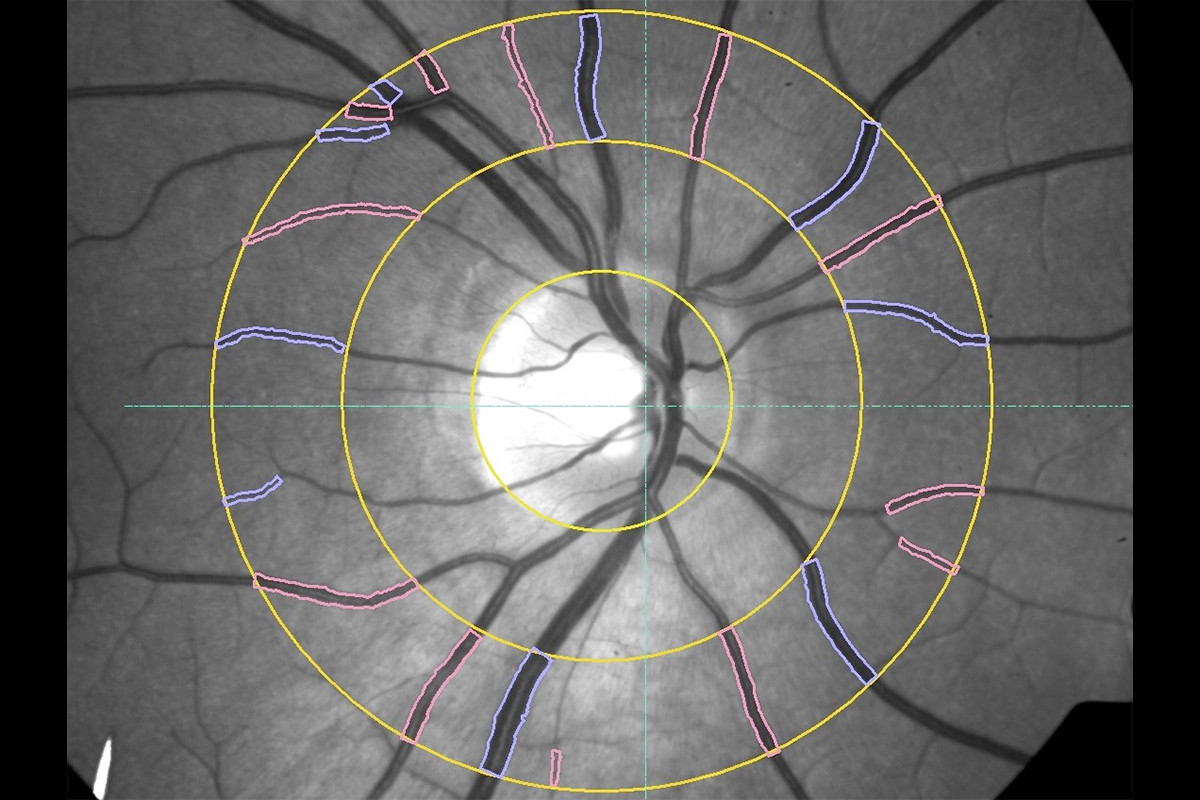

VesselMap aric: Image of the ocular fundus with measuring rangeVesselMap aric: Image of the ocular fundus with measuring range

2. The fundus image is opened in the software and the papilla is marked. Therefore, a measurement grid is placed on the image.

3. Subsequently, within this measurement grid (ring zone), all essential arterial and venous vessels are marked manually by selecting and clicking on them.

4. The software now determines the vessel diameters according to the marked vessels and calculates the static vessel parameters.

The recording of the fundus images, determination of the parameters and evaluation of the static vessel parameters are carried out on the basis of the ARIC study.